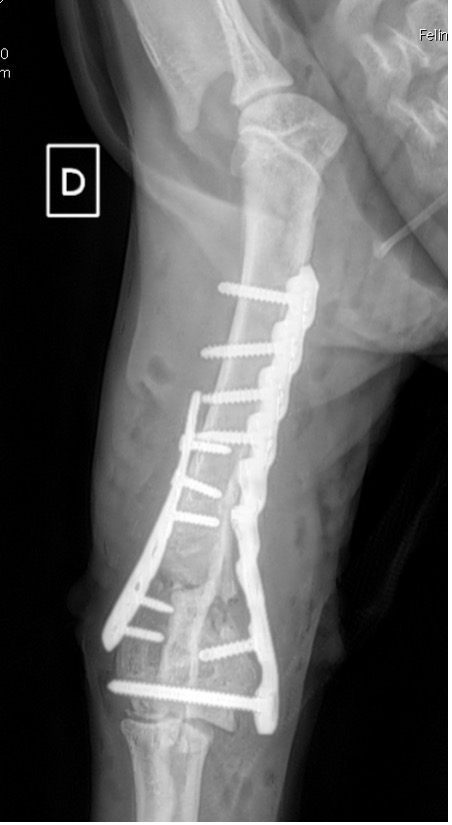

Notre préférence va vers le placement de deux plaques humérales : une médiale de la plus grande taille possible et l’autre latérale, généralement d’une taille inférieure à la première. Dans l’exemple 1 (chat européen), une plaque de 2 mm est utilisée médialement et une plaque de 1,5 mm latéralement. Dans l’exemple 2 (chien Malinois), une plaque de 3,5 mm est utilisée médialement et une plaque de 2,7 mm latéralement.

Exemple 1 :

Figure 2 : Post-Op Immédiat